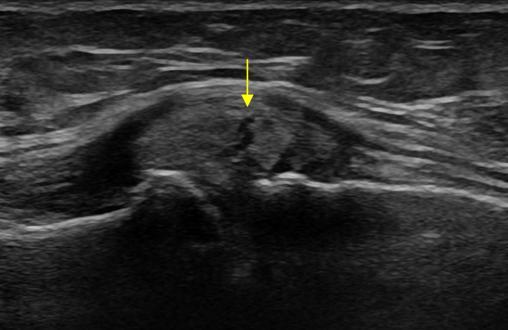

Meniscal Tears

Bulging meniscus with horizontal tear